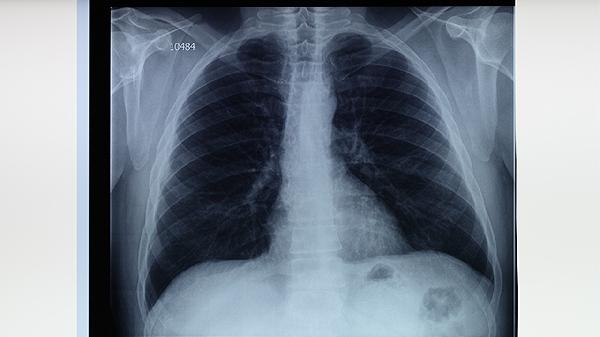

肺结核是我们周围多发的疾病,对肺健康产生严重影响和伤害,患肺结核给很多患者朋友带来麻烦,给他们带来痛苦。肺结核发生后,会出现什么样的症状呢?让我们一起来看看。早期病灶小或位于肺组织深处,多无异常体征。病变范围广,侧肺呼吸运动减弱,诊断浑浊,诊断时呼吸声减少,支气管肺泡呼吸声减少。肺结核多发于肺上叶尖